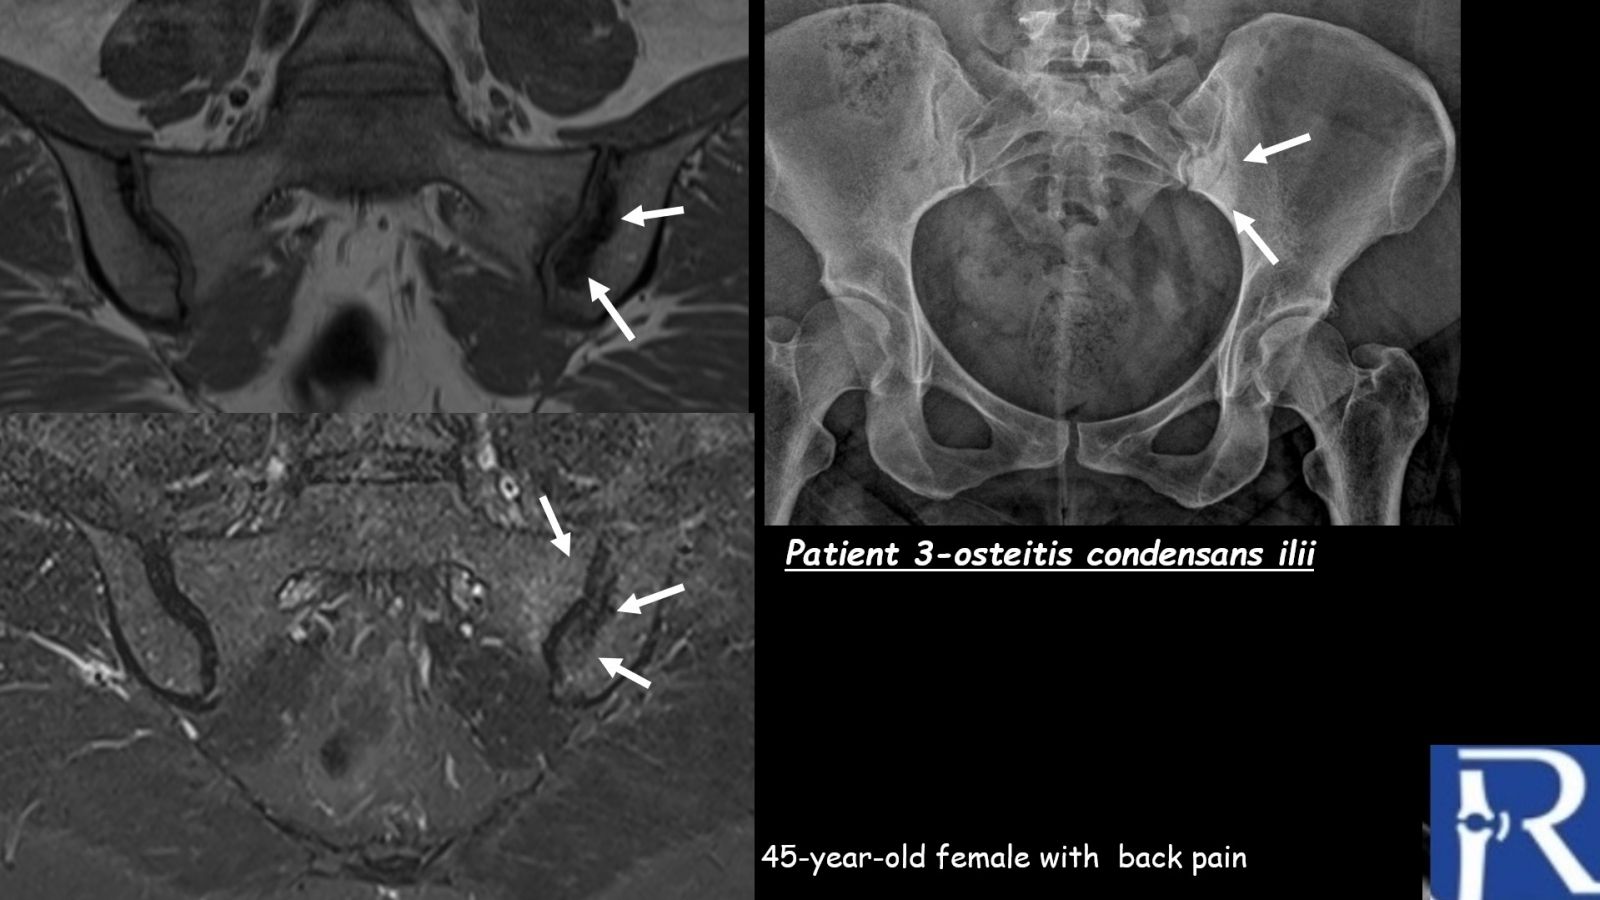

Case 3

Clinical presentation:

A 45-year-old woman presenting with back pain.

MRI findings:

MRI shows triangular-shaped periarticular sclerosis involving the left iliac bone, associated with mild bone marrow edema in the adjacent iliac and sacral bones at the left sacroiliac joint. The imaging findings are characteristic of osteitis condensans ilii.

Radiography:

Plain radiographs demonstrate triangular-shaped periarticular sclerosis of the left iliac bone.